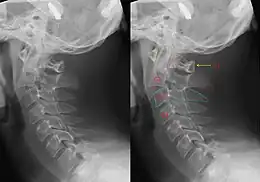

Hangman's fracture is the colloquial name given to a fracture of both pedicles, or partes interarticulares, of the axis vertebra (C2).[1]

The mechanism of the injury is forcible hyperextension of the head, usually with distraction of the neck. Traditionally this would occur during judicial hanging, when the noose was placed below the condemned subject's chin. When the subject was dropped, the head would be forced into hyperextension by the full weight of the body, a sufficient force to cause the fracture. However, despite its long association with judicial hangings, one study of a series of such hangings showed that only a small minority of hangings produced a hangman's fracture.[5]

Although a hangman's fracture is unstable, survival from this fracture is relatively common, as the fracture itself tends to expand the spinal canal at the C2 level. It is not unusual for patients to walk in for treatment and have such a fracture discovered on X-rays. Only if the force of the injury is severe enough that the vertebral body of C2 is severely subluxed from C3 does the spinal cord become crushed, usually between the vertebral body of C3 and the posterior elements of C1 and C2.